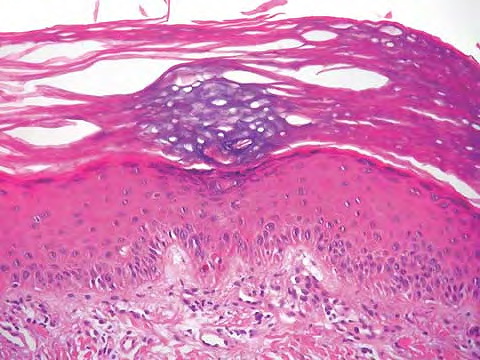

Parapsoriasis Large-plaque = نظير الصدف كبير اللويحات Parapsoriasis There are three entities described as parapsoriasis: small-plaque parapsoriasis, large-plaque parapsoriasis, and parapsoriasis variegata. Large-plaque parapsoriasis and parapsoriasis variegata are best considered as early stages of cutaneous T-cell lymphoma/mycosis fungoides. The small-plaque parapsoriasis is also known as xanthoerythrodermia perstans of Crocker and as digitate dermatosis . Pink-to-yellow, slightly scaly, oval or elongated, […]